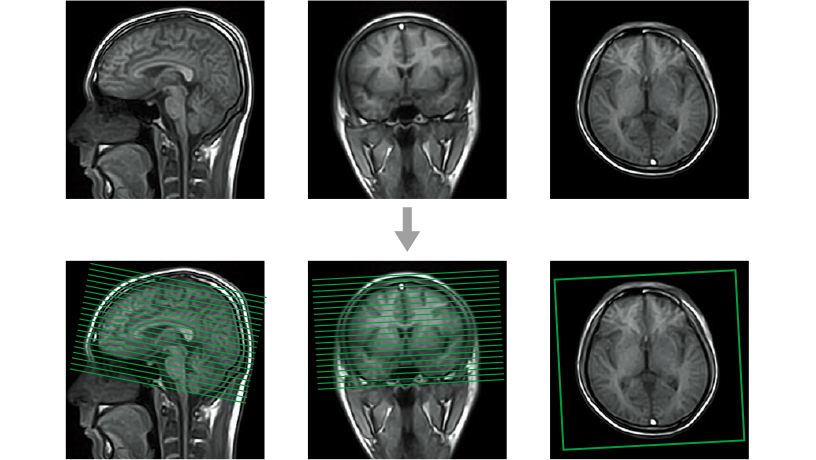

- AutoPose

Görüntülemede elde edilen yüksek uzamsal çözünürlüklü hacim verileri, MPR işlemede herhangi bir çapraz görüntülerini yeniden oluşturmak için kullanılabilir.Akıllı ÇALIŞMA